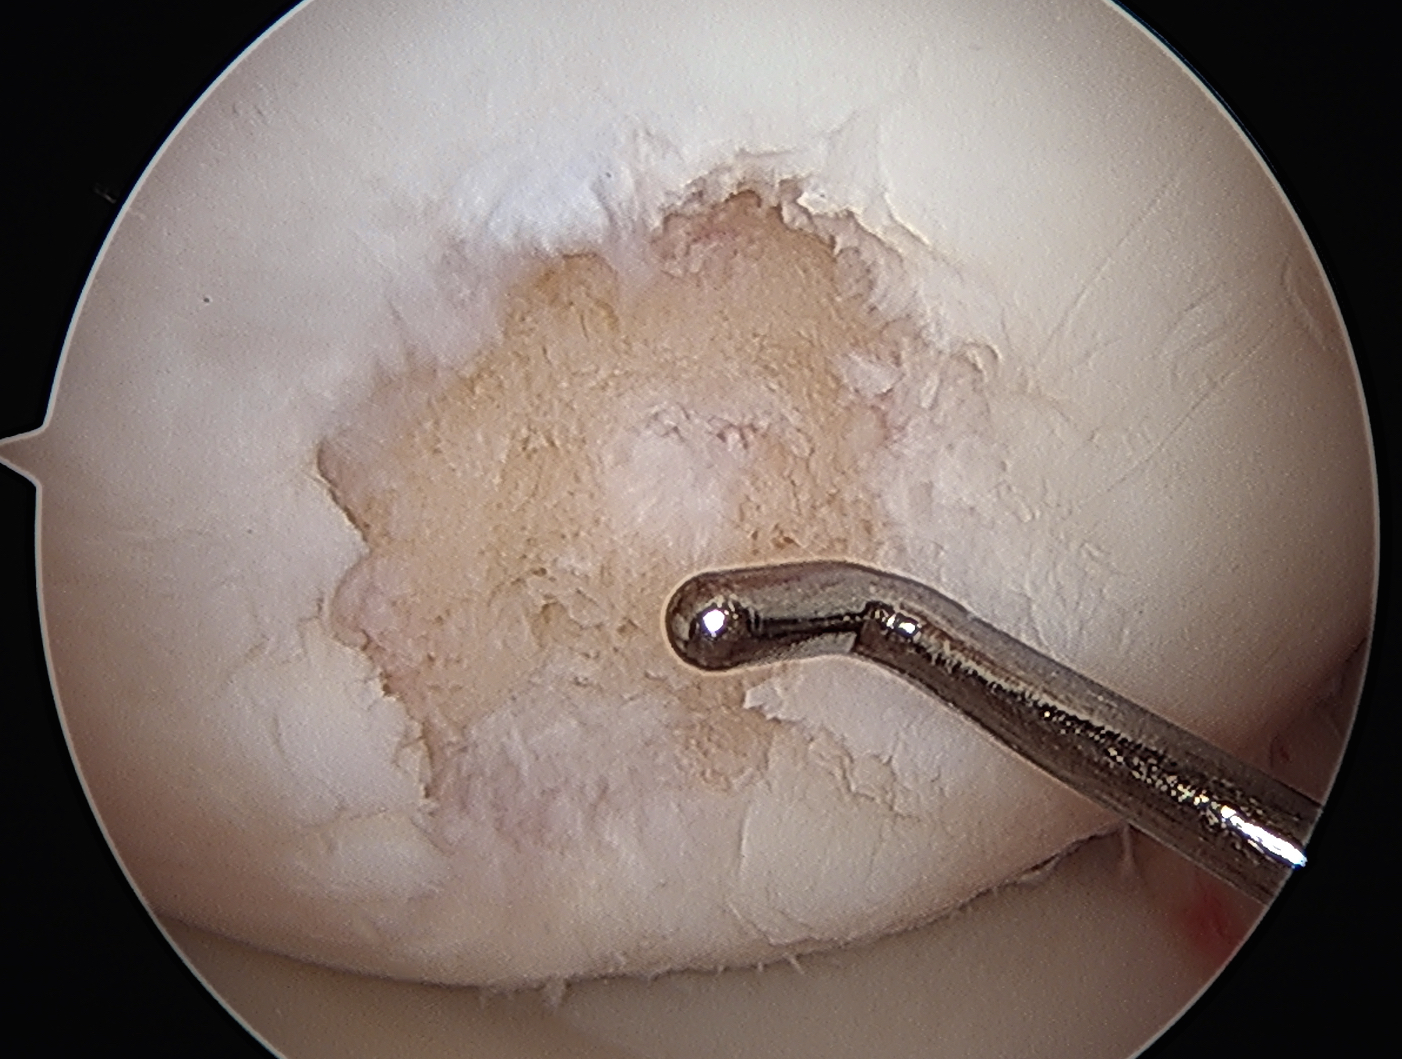

Grade 4: Exposed subchondral bone

Grade IV: Severely abnormal - cartilage lesion down to subchondral bone

Grade IV: cartilage lesion down to subchondral bone